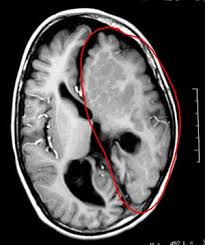

Hemisferectomía. Procedimiento neuroquirúrgico que consiste en la extracción o inhabilitación de un hemisferio cerebral (una de las mitades del cerebro). Este procedimiento es usado para tratar un gran número de trastornos convulsivos donde la fuente de la epilepsia se localiza en un área más o menos amplia de uno de los hemisferios del cerebro. Está únicamente reservada para casos extremos en que las crisis no hayan respondido a los medicamentos u otras cirugías menos invasivas.

La hemisferectomía tiene su indicación más frecuente en la hemiatrofia cerebral. Cuando la hemiatrofia se manifiesta clínicamente por: hemiplejía completa, ataques epilépticos focales, cambios del carácter sin disminución o con poca disminución del intelecto, debe practicarse la hemisferectomía; radiológicamente, cuando la neumoencefalografía muestra una atrofia unilateral del cerebro y cuando la electroencefalografía aporta datos de un foco epileptógeno unilateral. Si algunos datos de estos faltan, la indicación quirúrgica también es válida si existe una hemiplejía completa.

En la hemiatrofia cerebral, a veces está indicada una hemisferectomía subtotal, en la cual se conservan los lóbulos temporal y occipital para evitar la hemianopsia. Este tipo de hemisferectomía es planteable cuando el cuadro clínico no tiene hemianopsia, la aneumoencefalografía no muestra una atrofia considerable de estos lóbulos y la electroencefalografía no indica un foco epileptógeno, en ellos (se incluye la electrocorticografía durante la operación)